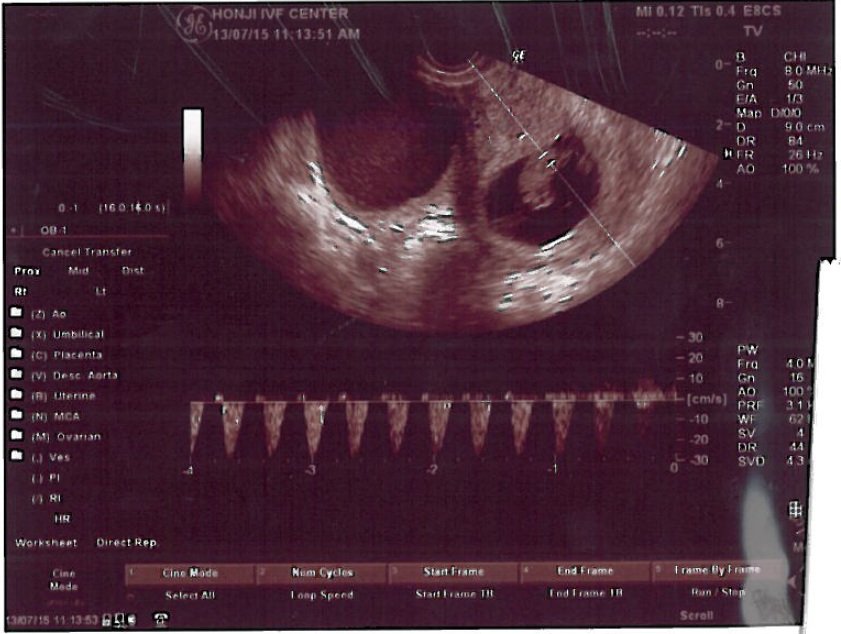

我們的過程算是有些特殊,因為是太太有些高齡(40歲)而且先生又有取精的問題(absence of ductus deferus 先天無輸精管症),因此聽說是一種較為困難畢業的例子。後來在張醫師的療程中,先是內人的少排卵針刺激及無麻醉取卵,再來是張醫師親自執行先生的無麻醉無開刀的副睪取精,然後馬上在實驗室精卵結合成受精卵並再約五天發育到囊胚,後才殖入終於順利懷孕。並且無論是取卵還是取精,雖然副睪取精手術過程中還是有些疼痛與刺痛卻尚在可忍受得住的範圍,因為先前傳統別家(北部醫學中心)的經驗是要全身麻醉手術且要數週的復原期,而張醫師的治療方式卻是令人驚訝地手術後休息30分鐘後馬上可以走路回家,大約再需三天的稍稍療養(除不能劇烈運動)後就彷彿如常人無手術般地復原了!

這次在張醫師的精湛的手術、實驗室團隊的優良品管、懷孕初期的少量但精準的藥物與數據控制,這次我們終於懷孕了,聽到心跳的那一剎那,使我們體會到非常深刻的生命意義!